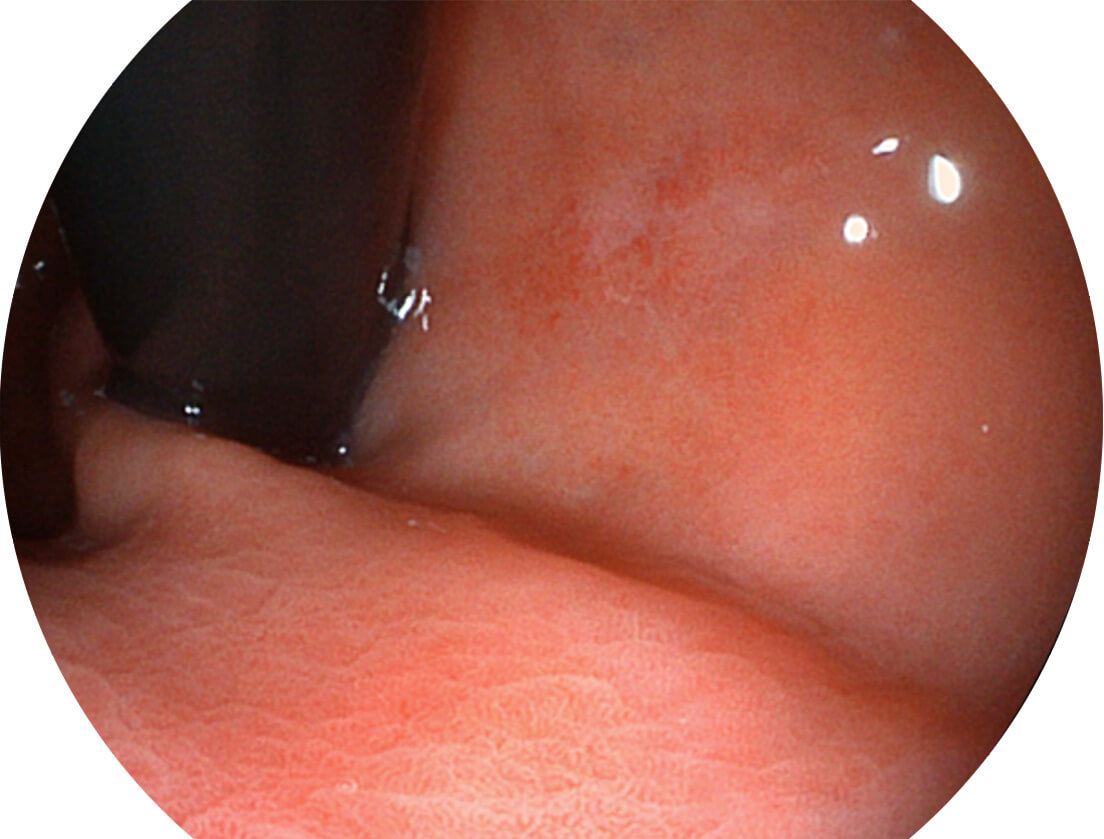

图像具有高亮度、高黏膜血管颜色对比度的特点,且不改变粘液、食物残渣、粪便的基本颜色,可在中远景下进行观察,助力消化道早期疾病的诊断。

白光图像

SFI图像